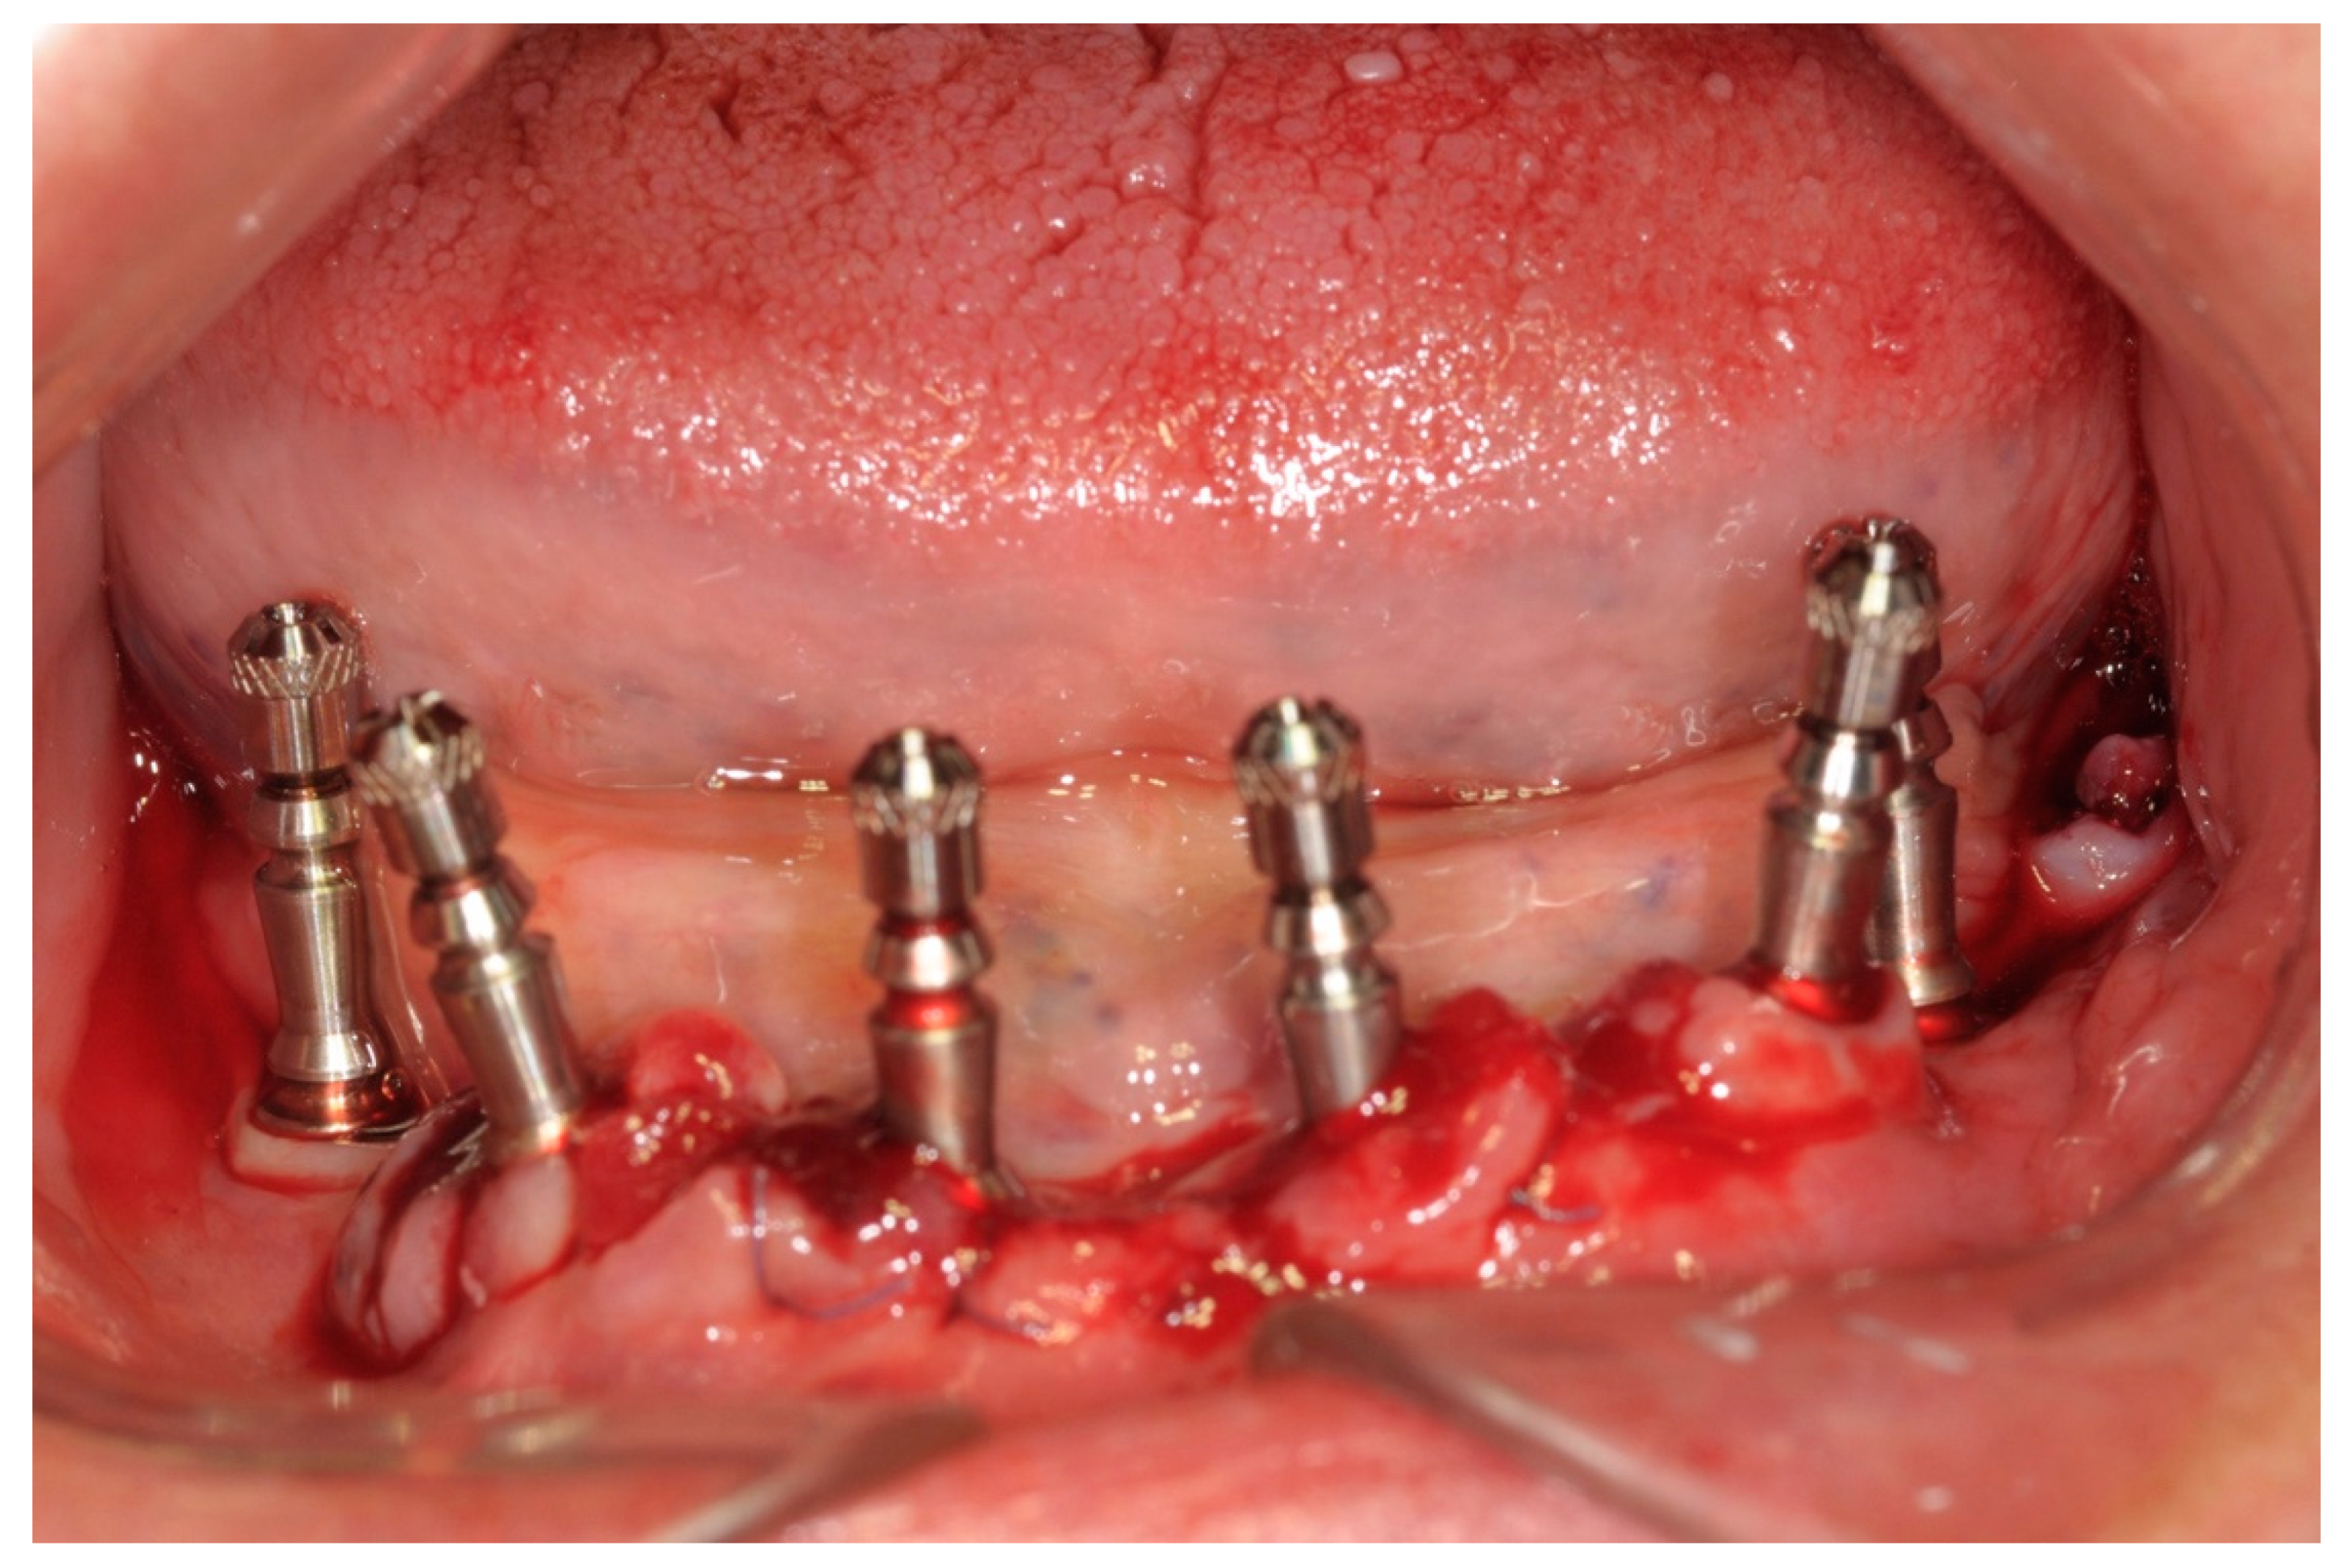

The peri-implant bone defects in the extraction sockets were grafted with a cortico-cancellous porcine bone (GTO, Tecnoss-Dental, Giaveno, Italy). Flat abutments (FlatOne®; Intra-Lock International®, Inc., Boca Raton, FL, USA) were then connected to the implants, and the flap was sutured (Figure 4).

Figure 4. Flat abutment connection.